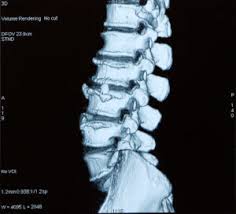

Causes Of Degenerative Disc Disease Aging Wear And Tear On The Spine